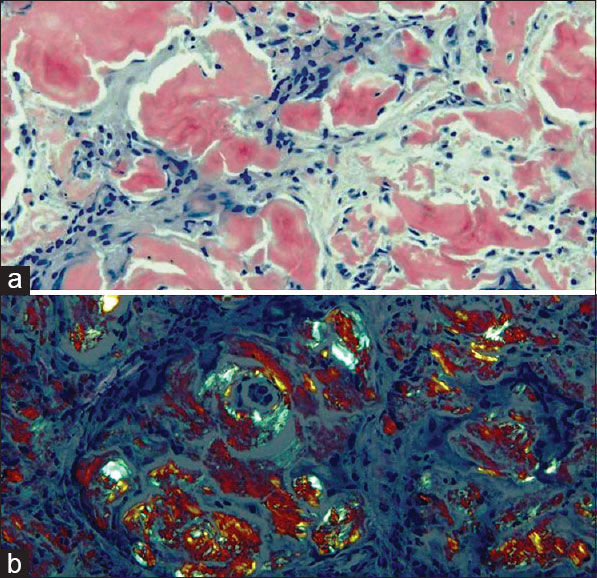

La tarda insorgenza e la non specificità dei sintomi sono ciò che rende pericolosamente subdola l’amiloidosi, che può essere diagnosticata con certezza solo attraverso un esame bioptico dei tessuti interessati, avvalendosi di particolari colorazioni istologiche come il Red Congo, che conferisce all’amiloide un colore pesca/rosato o verde brillante sotto la luce polarizzata.

Qui l’amiloide si deposita soprattutto a livello del glomerulo, porzione del rene deputata a filtrare il sangue facendo in modo che le proteine non si riversino nelle urine, danneggiandolo progressivamente.